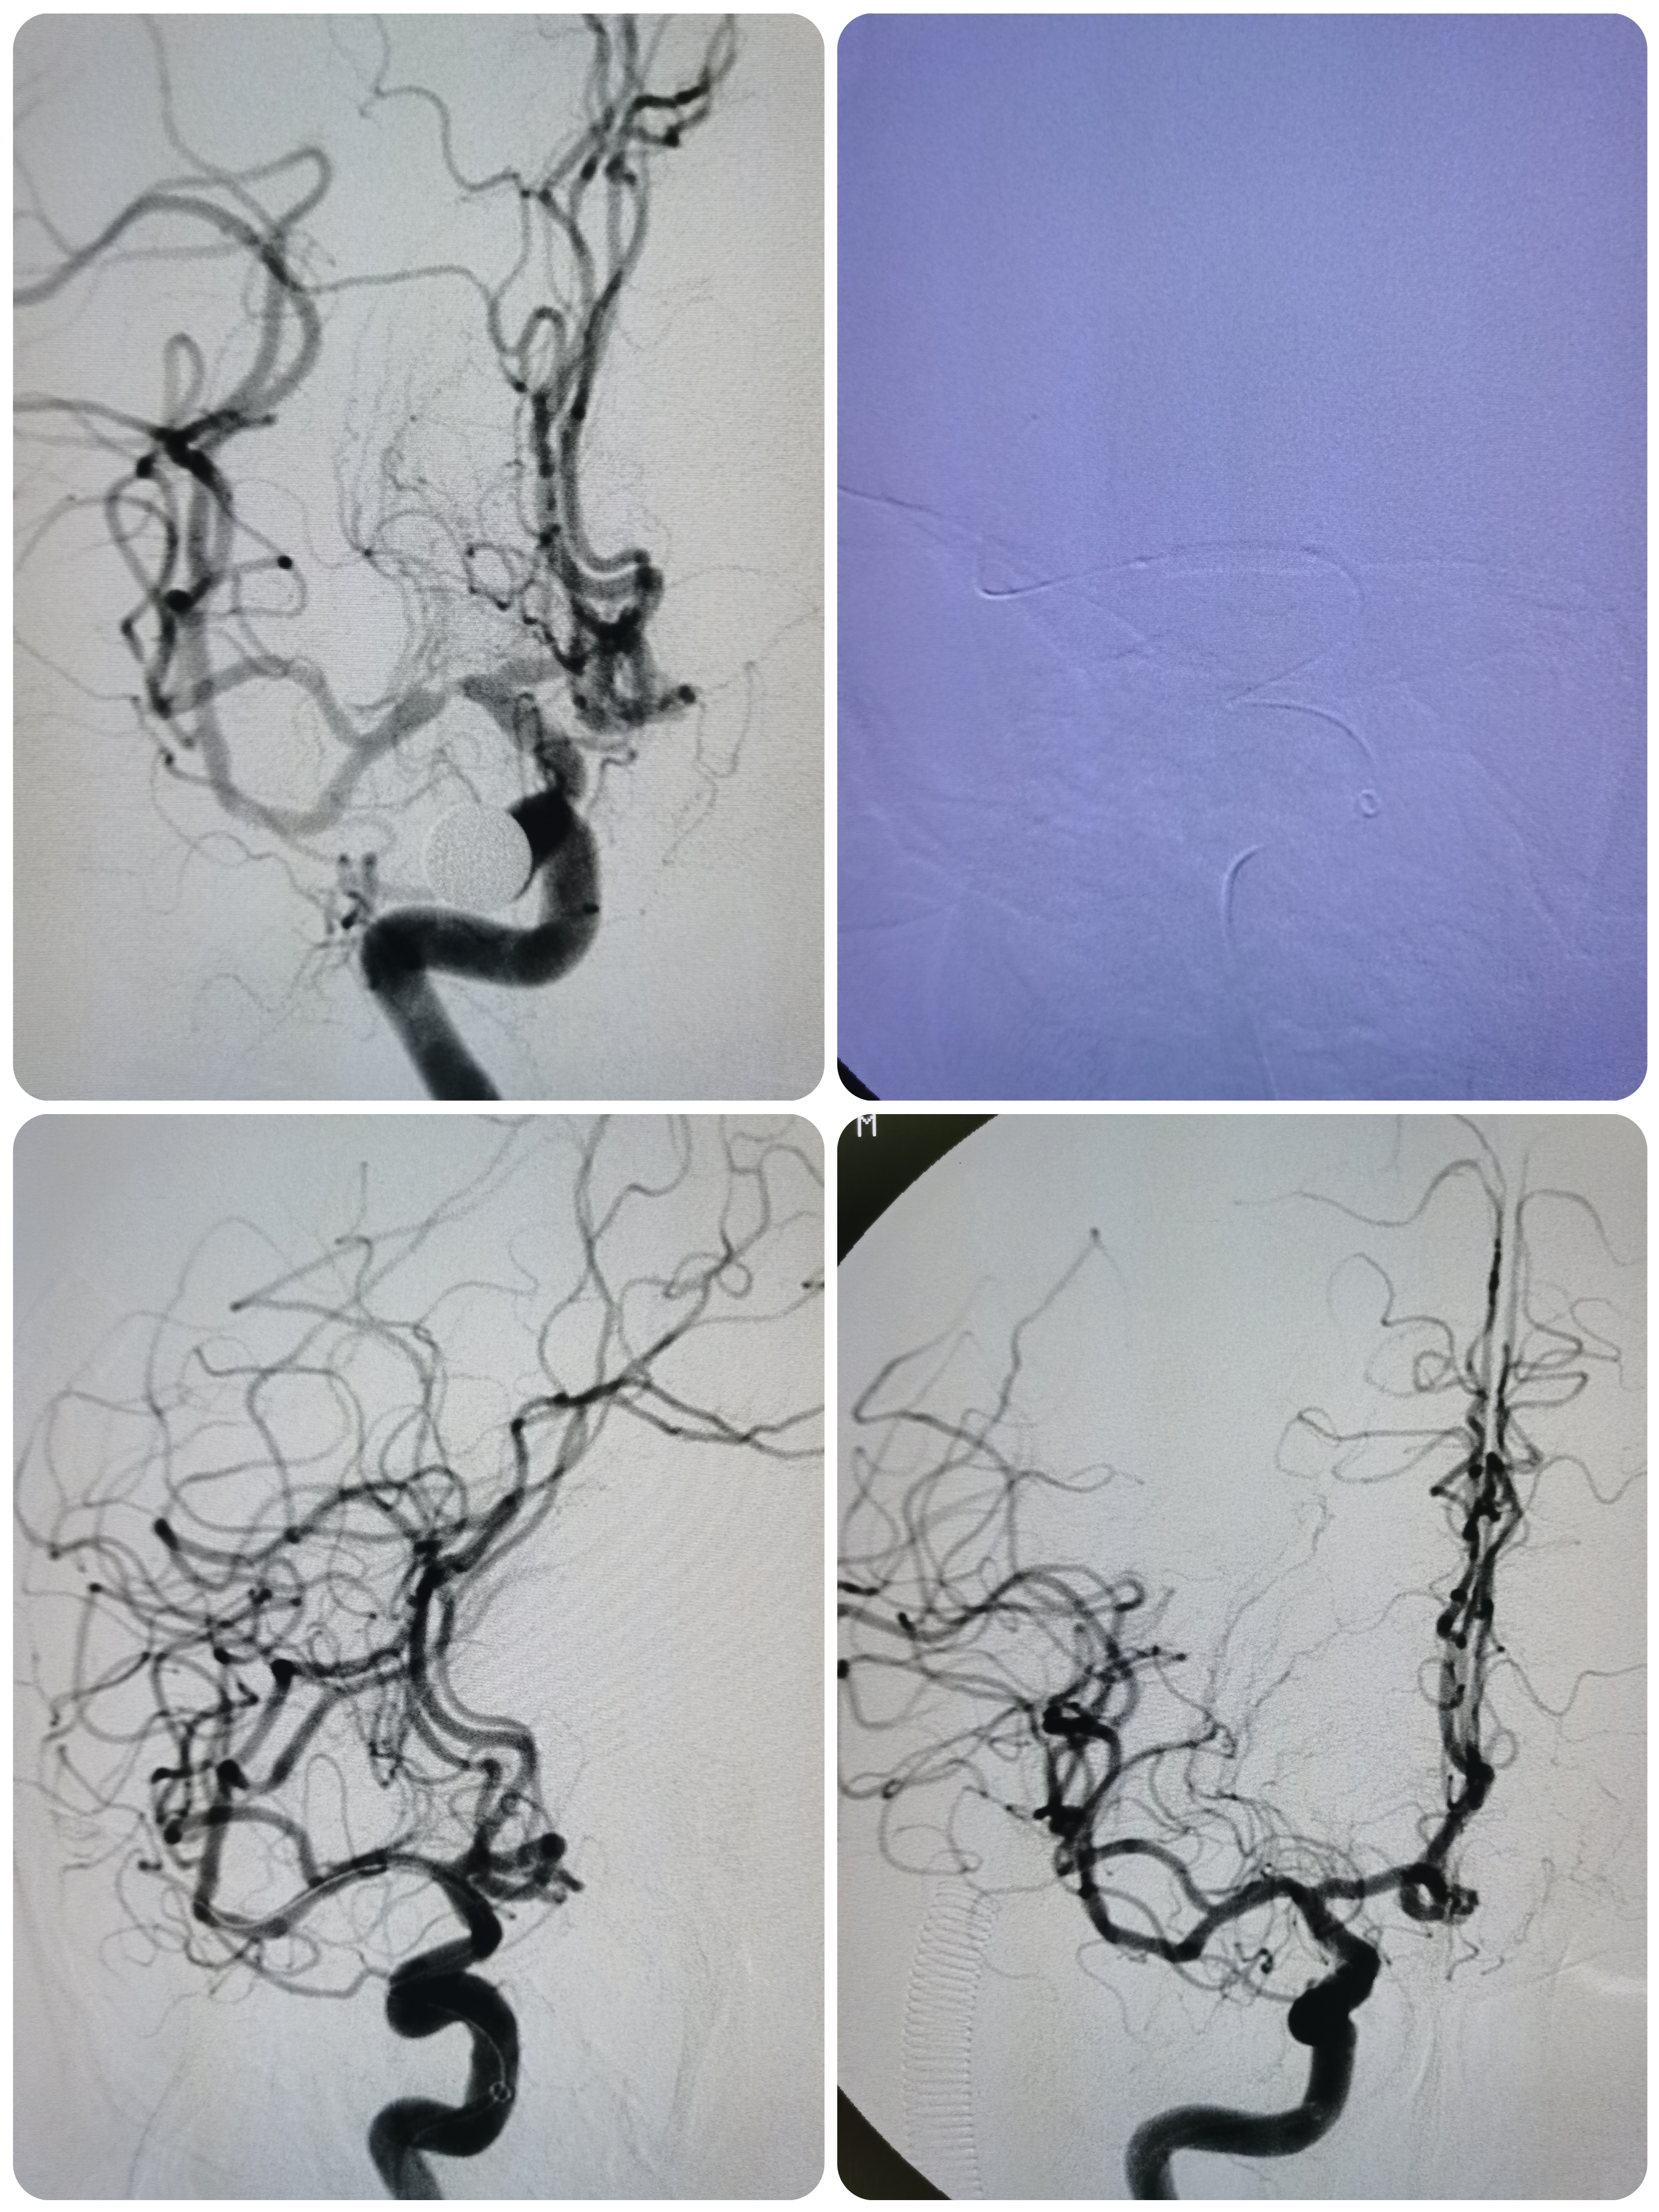

球扩后造影见狭窄解除,豆纹动脉显影良好,远端血供改善,未见夹层征象。

正位造影见狭窄解除,颅内血流通畅。

观察15分钟后造影未见明显弹性回缩。

侧位造影见颅内血流通畅。

球囊扩张后狭窄解除,决定不再植入支架,撤出导丝造影见血管通畅,遂逐级撤出各级导管,结束手术。

术前术后对比

3、球囊扩张后狭窄解除,无夹层征象,血流通畅,遂未再植入支架。